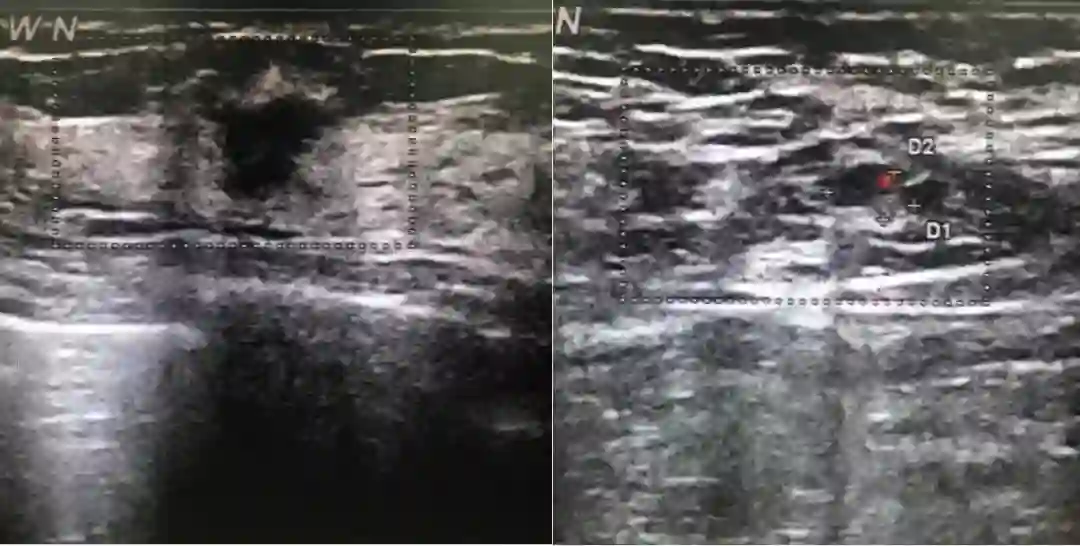

2018年8月15日行乳腺超声检查:右乳外上11mm×9mm低回声区,边界不清晰,内部回声不均匀,未见明显血流信号。右腋下见淋巴结7mm×4mm,皮质稍增厚。超声诊断:双乳小叶增生,右乳低回声(BI-RADS 4B),右腋下淋巴结。2018年8月27日行双乳钼靶检查:双乳未见明显异常(BI-RADS 1)。

图1. 2018年8月15日行乳腺超声检查